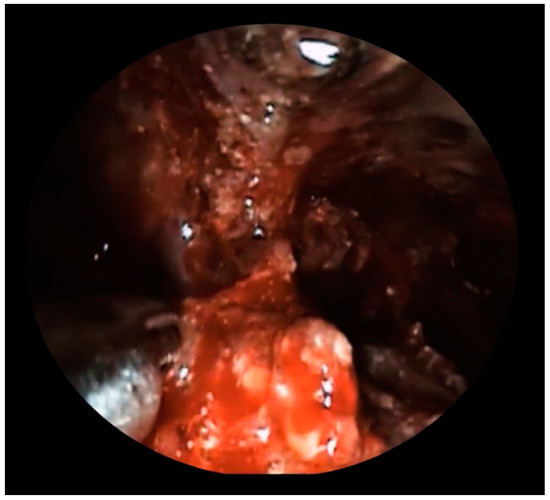

2. Case Presentation